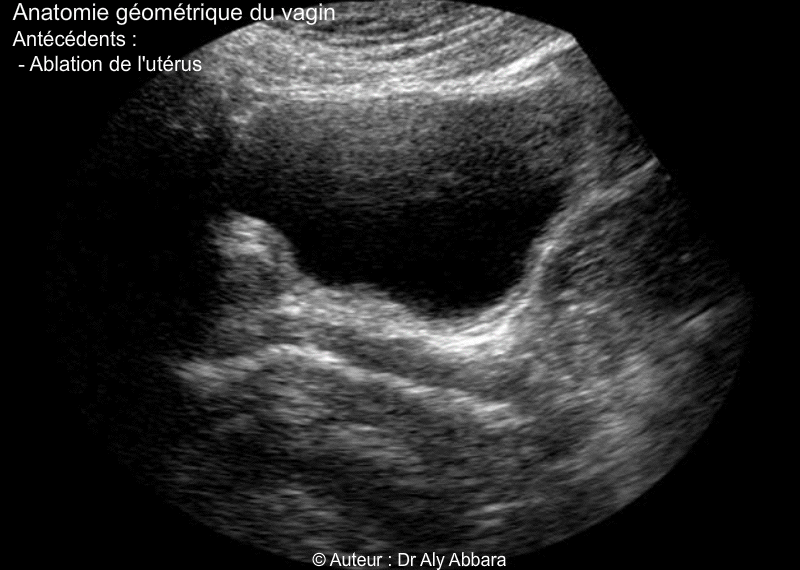

Vagin de femme adulte ayant déjà eu une hystérectomie totale - Rapports anatomiques - Echographie

Vagin : ses rapports anatomiques avec les organes avoisinants chez une femme

aynat dans ses antécédents une hystérectomie totale

(Coupe échographique sagittale médiane du pelvis - vessie pleine).